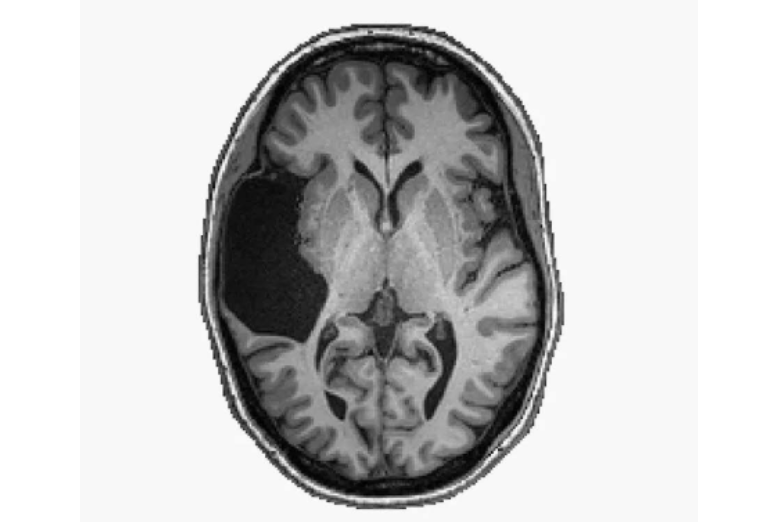

Една жена на која од детството ѝ недостига дел од мозокот успеала да заврши факултет и зборува два јазици.

Жената, чиј идентитет не е откриен, им напишала на двајца научници од Технолошкиот институт во Масачусетс во 2016 година објаснувајќи им дека има необичен мозок. Она што е чудно кај нејзиниот мозок е што му недостига голем дел од левата страна, за која научниците мислат дека е одговорна за говорот.

Истражувачите ја упатиле жената кај когнитивниот невролог Евелин Федоренко, која напишала труд за нејзиниот мозок. Фактот дека недостига голем дел од мозокот на жената, која сега е во шестата деценија од животот, немал голем ефект врз нејзиниот живот. Таа дипломирала на факултет, имала импресивна кариера и освен англиски јазик, одлично зборува и руски.

Таа дознала дека нејзиниот мозок е необичен во 1987 година кога ја скенирала главата поради други причини. Аномалијата веројатно се појавила поради мозочен удар кој се случил кога таа била бебе.

Во текот на годините таа се обратила на разни доктори кои ѝ рекле дека тоа едноставно нема смисла. Според Федоренко, која последна го истражувала мозокот на жената, точната улога на секој дел од мозокот треба да се открие, како и начинот на кој целиот систем функционира.